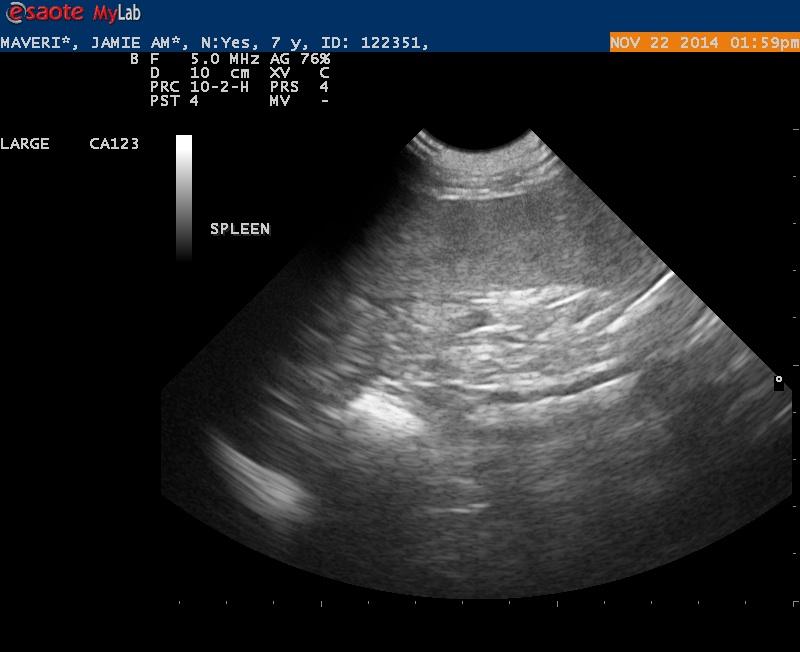

Maverick is a 7 1/2 year old Lab with 2 fairly large cutaneous mast cell tumors.

On x-rays the spleen was prominent but not overly enlarged.

Ultrasound findings were within normal limits. I did not appreciate any lymphadenopathy.

The spleen on first glance appeared to be normal- but when I went back and looked at my images I was wondering if the echotexture was a bit coarse.

1. Do you see any abnormalities with this spleen making it worthwhile to get an aspirate?